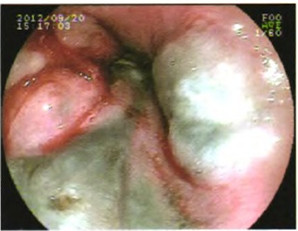

胃镜检查(图1)示:距门齿32cm以下见片状黑色黏膜及隆起灶,贲门近胃底处可见一大小约0.8cm×l.Ocm的半球形隆起灶,胃镜诊断为食管下段、贲门黑色隆起性质待查,考虑为食管癌。

图1 胃镜检查见片状黑色黏膜及隆起灶,贲门近胃底处可见半球形隆起灶